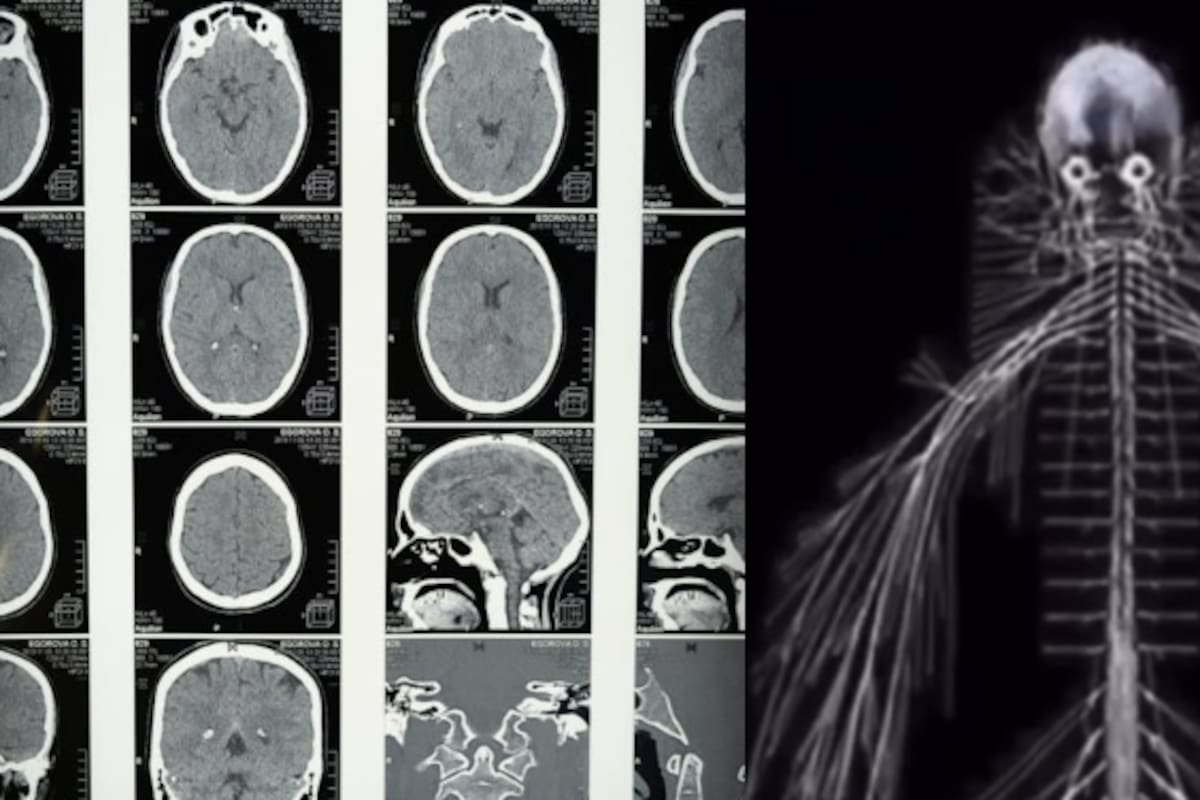

Tras su muerte, su cuerpo fue utilizado por el anatomista Dr. Rufus B. Weaver para realizar una disección completa del sistema nervioso humano, un logro sin precedentes en esa era.

Esta disección no solo sorprendió a la comunidad científica de la época, sino que también brindó valiosos conocimientos que ayudaron a avanzar en la comprensión de la anatomía humana, particularmente del sistema nervioso.

El cuerpo de Harriet fue preservado y exhibido como un modelo educativo, y su influencia se sintió profundamente en la medicina de la época.